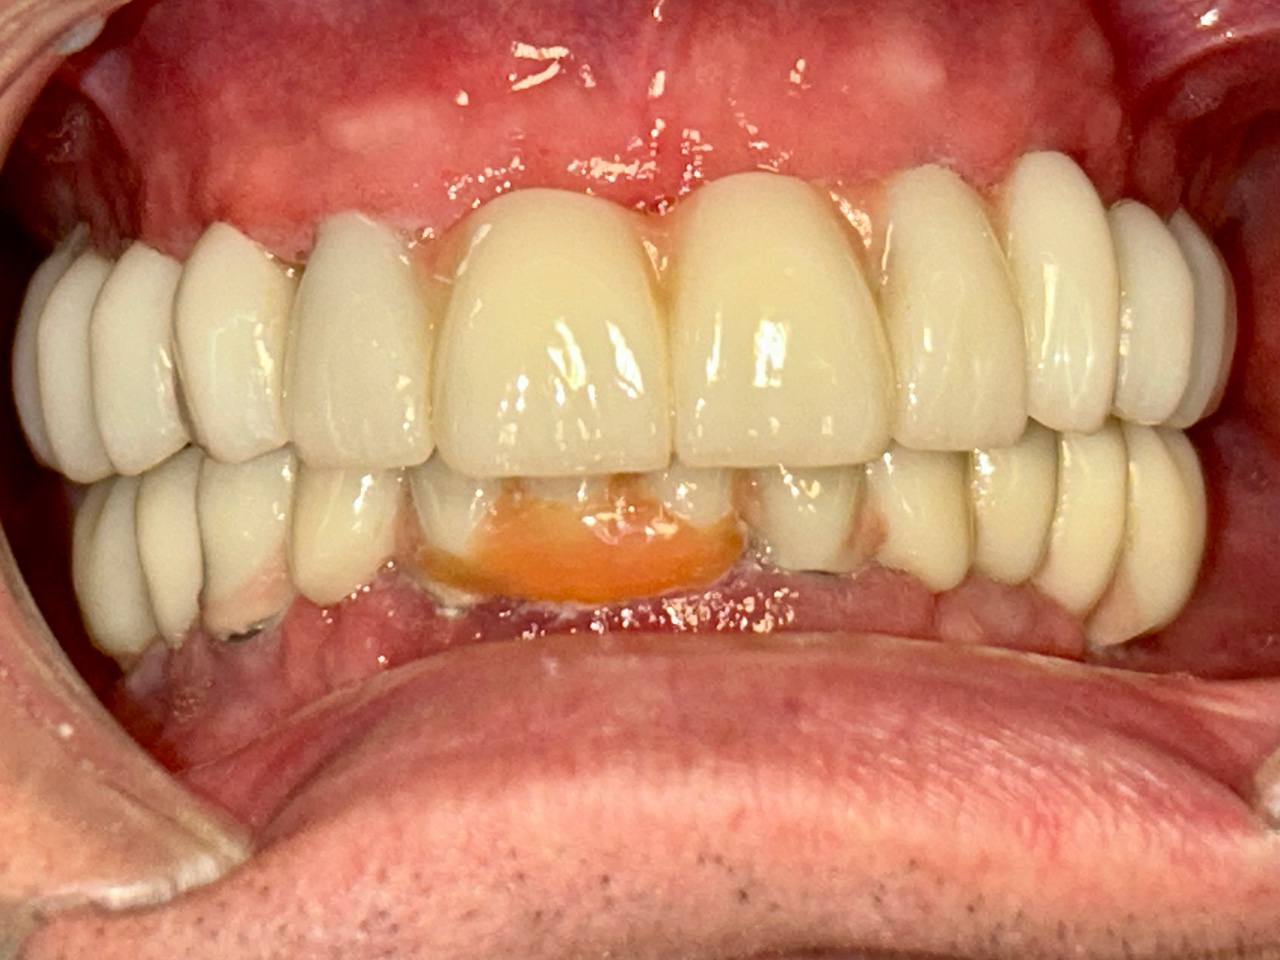

Teljes fogatlanság helyreállítása 2 nap alatt

Teljes fogatlanság helyreállítása 2 nap alatt azonnal terhelhető svájci IHDE implantátumokkal és PMMA műanyag hidakkal. Intraorális szkennerrel vettünk lenyomatot az implantáció után, és erre a digitális mintára készítette el a fogtechnika a hidak digitális tervezését, majd faragta ki műanyagból. Ezt a gyors munkát az azonnal terhelhető implantátumok és a digitális lenyomat, tervezés segítségével tudtuk megcsinálni mindössze 2 nap alatt. Dr. Kelemen Péter és a Symbion Fogtechnika munkája.